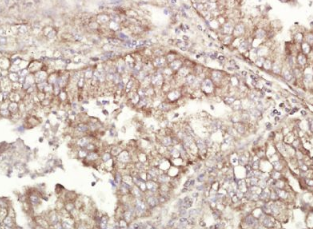

多聚甲醛固定,石蜡包埋(人肺癌);用柠檬酸钠缓冲液(pH6.0)煮沸15min后获得抗原;用3%过氧化氢阻断内源性过氧化物酶20分钟;在37℃下封闭缓冲液(正常山羊血清)30min;在1∶400 O下用(ALDH1)多克隆抗体进行抗体孵育。在4°C下观察,然后用共轭二次进行20分钟的DAB染色。